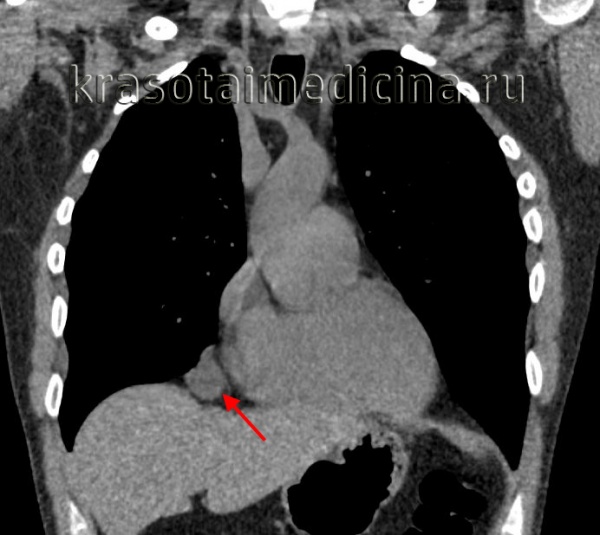

КТ ОГК. Массивное объемное образование верхнего средостения с объемным воздействием на трахею, исходящее из щитовидной железы.